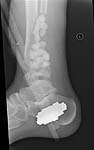

30 year old male, 10 weeks out from open fracture of distal tibia. Large anterolateral flap which looks healthy and just needs some STSG. Now shows up in my clinic. Slightly decreased sensation in dorsal foot, plantar normal. Decreased toe extension presumably from loss of anterior compartment and muscle damage.

My vote is acute shortening, tibio-talar fusion, re-lengthening through a proximal corticotomy (bifocal compression-distraction).

Acute shortening to till you get bone contact between the proximal and distal fragments.

Minimal internal fixation oriented tranversely, subchondral, to secure the medial malleolus

Fill in the remaining area with cancellous bone graft Lengthen thru a proximal corticotomy

Sacrificing the distal fragment entirely, and aiming for a tibio talar fusion is another option....

I favor shortening, and trying to preserve the ankle segment with some internal fixation- plate vs crossed screws. Bone graft well. Ankle motion is sometimes suprising because of the shortening. Let this heal, then lengthen above using your method of choice. I prefer monorail technique.